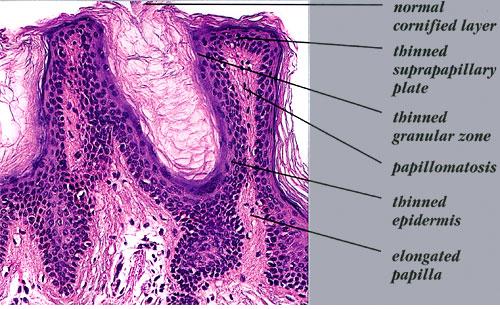

Histologic examination reveals hyperkeratosis and papillomatosis but only slight, irregular acanthosis and usually no hyperpigmentation. Thus, the term acanthosis nigricans has little histologic justification.

In a typical lesion, the dermal papillae project upward as finger-like projections. The valleys between the papillae show mild to moderate acanthosis and are filled with keratotic material . Hom pseudocysts can occur in some cases . The epidermis at the tips of the papillae and often also on the sides of the protruding papillae appears thinned.

Slight hyperpigmentation of the basal layer is demonstrable with silver nitrate staining in some cases but not in others . The brown color of the lesions is caused more by hyperkeratosis than by melanin.